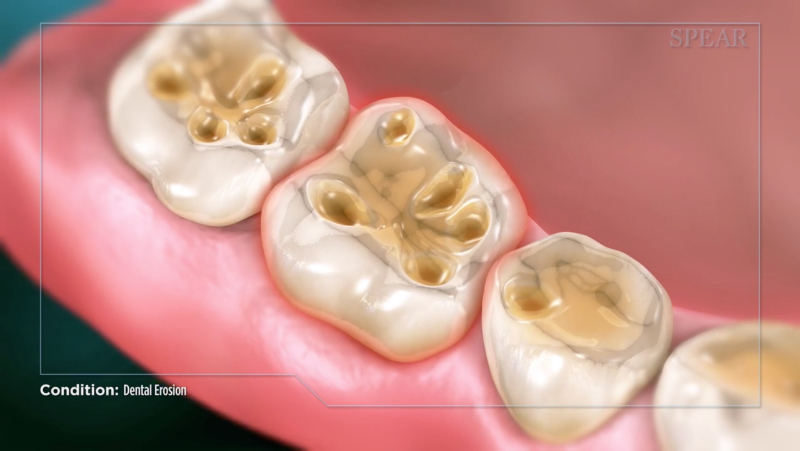

Describing clinical conditions to the patient is one of the most important steps during treatment. At my practice in Mexico City, we use Spear’s Patient Education videos consistently with great success to achieve better communication and understanding.

The dental erosion video (Fig. 6) is a one-minute, narrated animation using lay terms to define the condition and explain its leading causes.

One additional procedure we usually use to increase patients’ awareness is to show a still image from the Patient Education video alongside a photograph of the patient’s clinical condition. This truly helps them visualize and further understand the need for therapy and the harmful potential consequences of inaction.